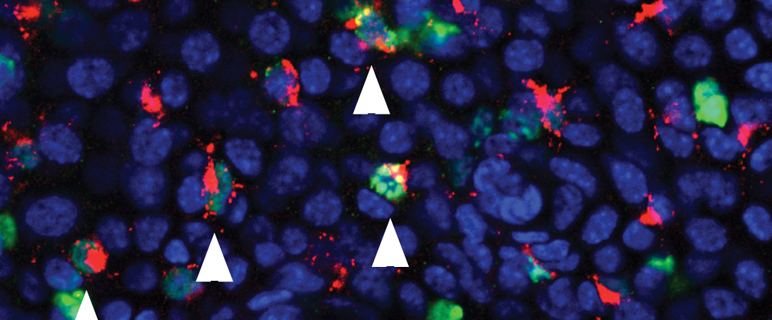

Eine in synergetischer Kooperation mit dem Team um Univ.-Prof. Lukas Huber vom Innsbrucker Biozentrum entstandene und soeben im Fachjournal BLOOD veröffentlichte Arbeit gewährt nun neue Einblicke in die Homöostase der Langerhanszellen. Erstautor Dr. Florian Sparber aus dem Team um Prof. Romani konnte sich dabei auf Vorarbeiten aus dem Biozentrum stützen, die auf die Signalweiterleitung in Zellen fokussieren. Die Forscher:innen um Prof. Huber klärten in einer Reihe von Arbeiten die zellbiologische Funktion des zellulären Adaptermoleküls p14 als Teil des LAMTOR Komplexes – ein Verband aus fünf Regulatorproteinen – auf. Schon vor einigen Jahren gelang etwa der Nachweis, dass das Fehlen von p14 zu Unordnung in der Zelle führt, wodurch wichtige Akteure für die Weiterleitung von Signalen nicht mehr zur rechten Zeit am rechten Platz sind. Eine komplexe Störung des Immunsystems ist die Folge. p14 dient also vor allem der räumlichen Koordination von Signaltransduktionsprozessen an der Membran von Endosomen (intrazelluläre Vesikel). „Endosomen spielen in den Dendritischen Zellen eine wichtige Rolle bei der Aufnahme von Antigenen. Es lag daher nahe, die Rolle des p14 Moleküls speziell und exklusiv in Dendritischen Zellen zu studieren. Anhand von Mausmodellen, in denen p14 selektiv in Dendritischen Zellen bzw. in Langerhanszellen eliminiert wurde, stellten wir überraschenderweise fest, dass die epidermalen Langerhanszellen in diesen Mäusen praktisch zur Gänze fehlten“, erzählt Erstautor Sparber, der mit dieser, über vier Jahre beanspruchenden Arbeit im Rahmen des Doktoratsprogramms Molecular Cell Biology (MCB) zum PhD promovierte. Damit gelang der Nachweis, dass der Zusammenbruch des Langerhanszell-Netzwerkes durch das Fehlen von p14 und dadurch induzierte Störungen in den zentralen mTOR und ERK Signaltransduktionswegen veursacht wird, was verringerte Zellteilung und vermehrten Zelltod (Apoptose) der Langerhanszellen kurz nach der Geburt zur Folge hatte.

The late endosomal adaptor molecule p14 (LAMTOR2) represents a novel regulator of Langerhans cell homeostasis. Florian Sparber, Julia M. Scheffler, Nicole Amberg, Christoph H. Tripp, Valeska Heib, Martin Hermann,Sonja P. Zahner, Björn E. Clausen, Boris Reizis, Lukas A. Huber, Patrizia Stoitzner and Nikolaus Romani. Blood. 2014 Jan 9;123(2):217-27;